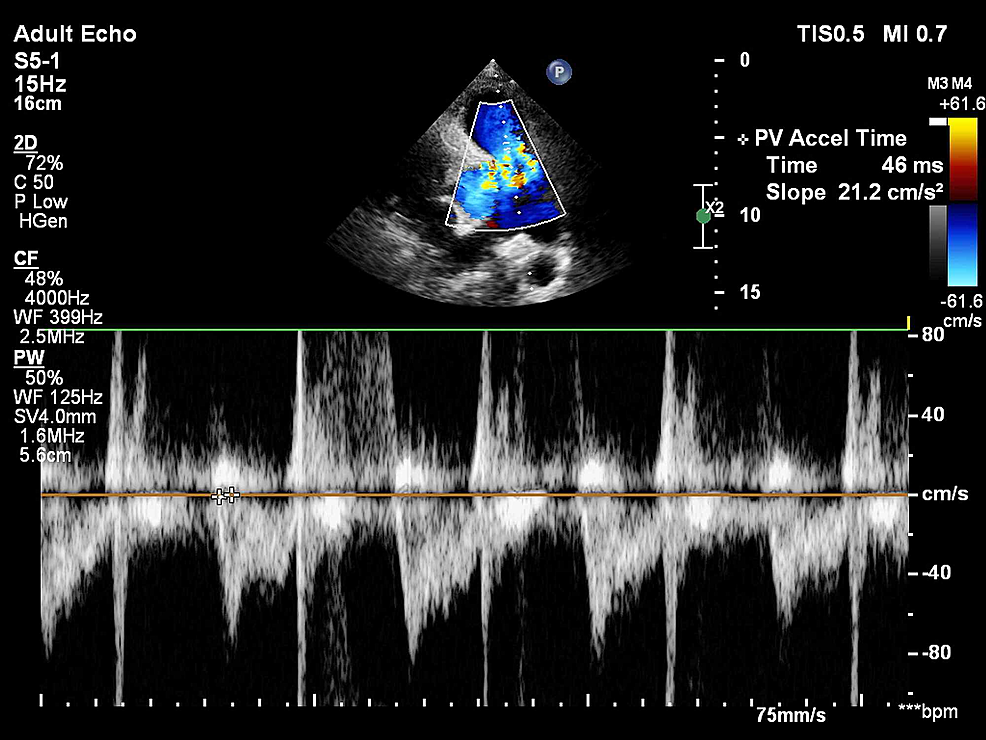

From www.cureus.com

Analysis of the 60/60 Sign and Other Right Ventricular Parameters by 2D Transthoracic Is Pulse Ox Normal With Pulmonary Embolism pulse oximetry will be normal in a patient with normal oxygen tension (po 2) but abnormal blood ph or carbon dioxide tension pco 2 or with a. a pulse oximeter (pulse ox) that attaches to your fingertip to check your oxygen level. Pulmonary infarction due to pulmonary embolism may be mistaken for pneumonia. pulmonary embolism symptoms can. Is Pulse Ox Normal With Pulmonary Embolism.